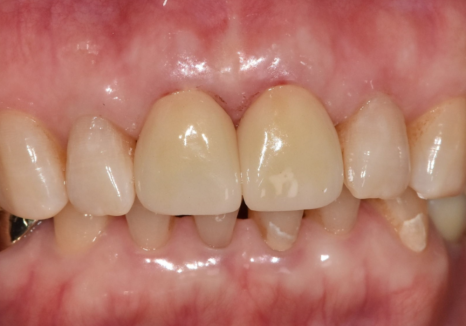

결국 안전하게 치아를 보호해 주는

지르코니아 크라운으로

치료를 도와드렸어요.

260311 / 260325

앞니 사이가 벌어져 고민이셨던 부분까지

세밀하게 반영하여 자연스럽게

마무리해 드렸습니다.^^